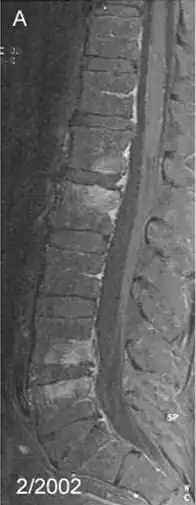

Spondylitis due to Tropheryma whipplei: Contrast-enhanced, T1 weighted fat suppressed magnetic resonance imaging demonstrating contrast enhancing lesions of spondylitis in the first (L1) and second (L2), as well as fourth (L4) and fifth (L5) lumbar vertebra, sparing the intervertebral discs | |

Spondylitis is an inflammation of the vertebrae. It is a form of spondylopathy. In many cases, spondylitis involves one or more vertebral joints, as well, which itself is called spondylarthritis.